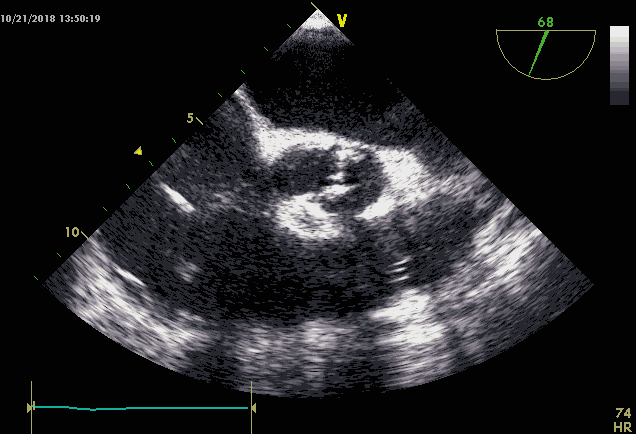

>>心超:

重度主动脉瓣狭窄伴反流,室间隔及左室壁增厚,左房扩大伴二尖瓣反流,右房扩大伴三尖瓣反流,主动脉增宽,左室舒张功能减退。

术前心超提示type1型二叶瓣,闭合受限,返流明显